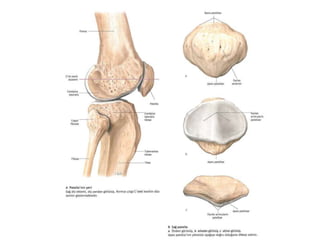

Art. bicondylaris

• Dış bükey eklem yüzü iki

kondil, içbükey eklem yüzü

ise sığ çukur şeklinde olan

eklemlerdir. Art. genus bu

eklem tipinin tipik örneğidir.

Hareket bakımından

menteşe şeklinde ekleme

(ginglymus) benzer ancak

flexion-extansiyon dışında,

bazı pozisyonlarda çok azda

olsa rotasyon ve yan tarafa

kayma hareketleri yapabilir.

Bir diğer örnek; art.

talocruralis'dir.

Art. bicondylaris • Dışbükey eklem yüzü iki kondil, içbükey eklem yüzü ise sığ çukur şeklinde olan eklemlerdir. Art. genus bu eklem tipinin tipik örneğidir. Hareket bakımından menteşe şeklinde ekleme (ginglymus) benzer ancak flexion-extansiyon dışında, bazı pozisyonlarda çok azda olsa rotasyon ve yan tarafa kayma hareketleri yapabilir. Bir diğer örnek; art. talocruralis'dir.